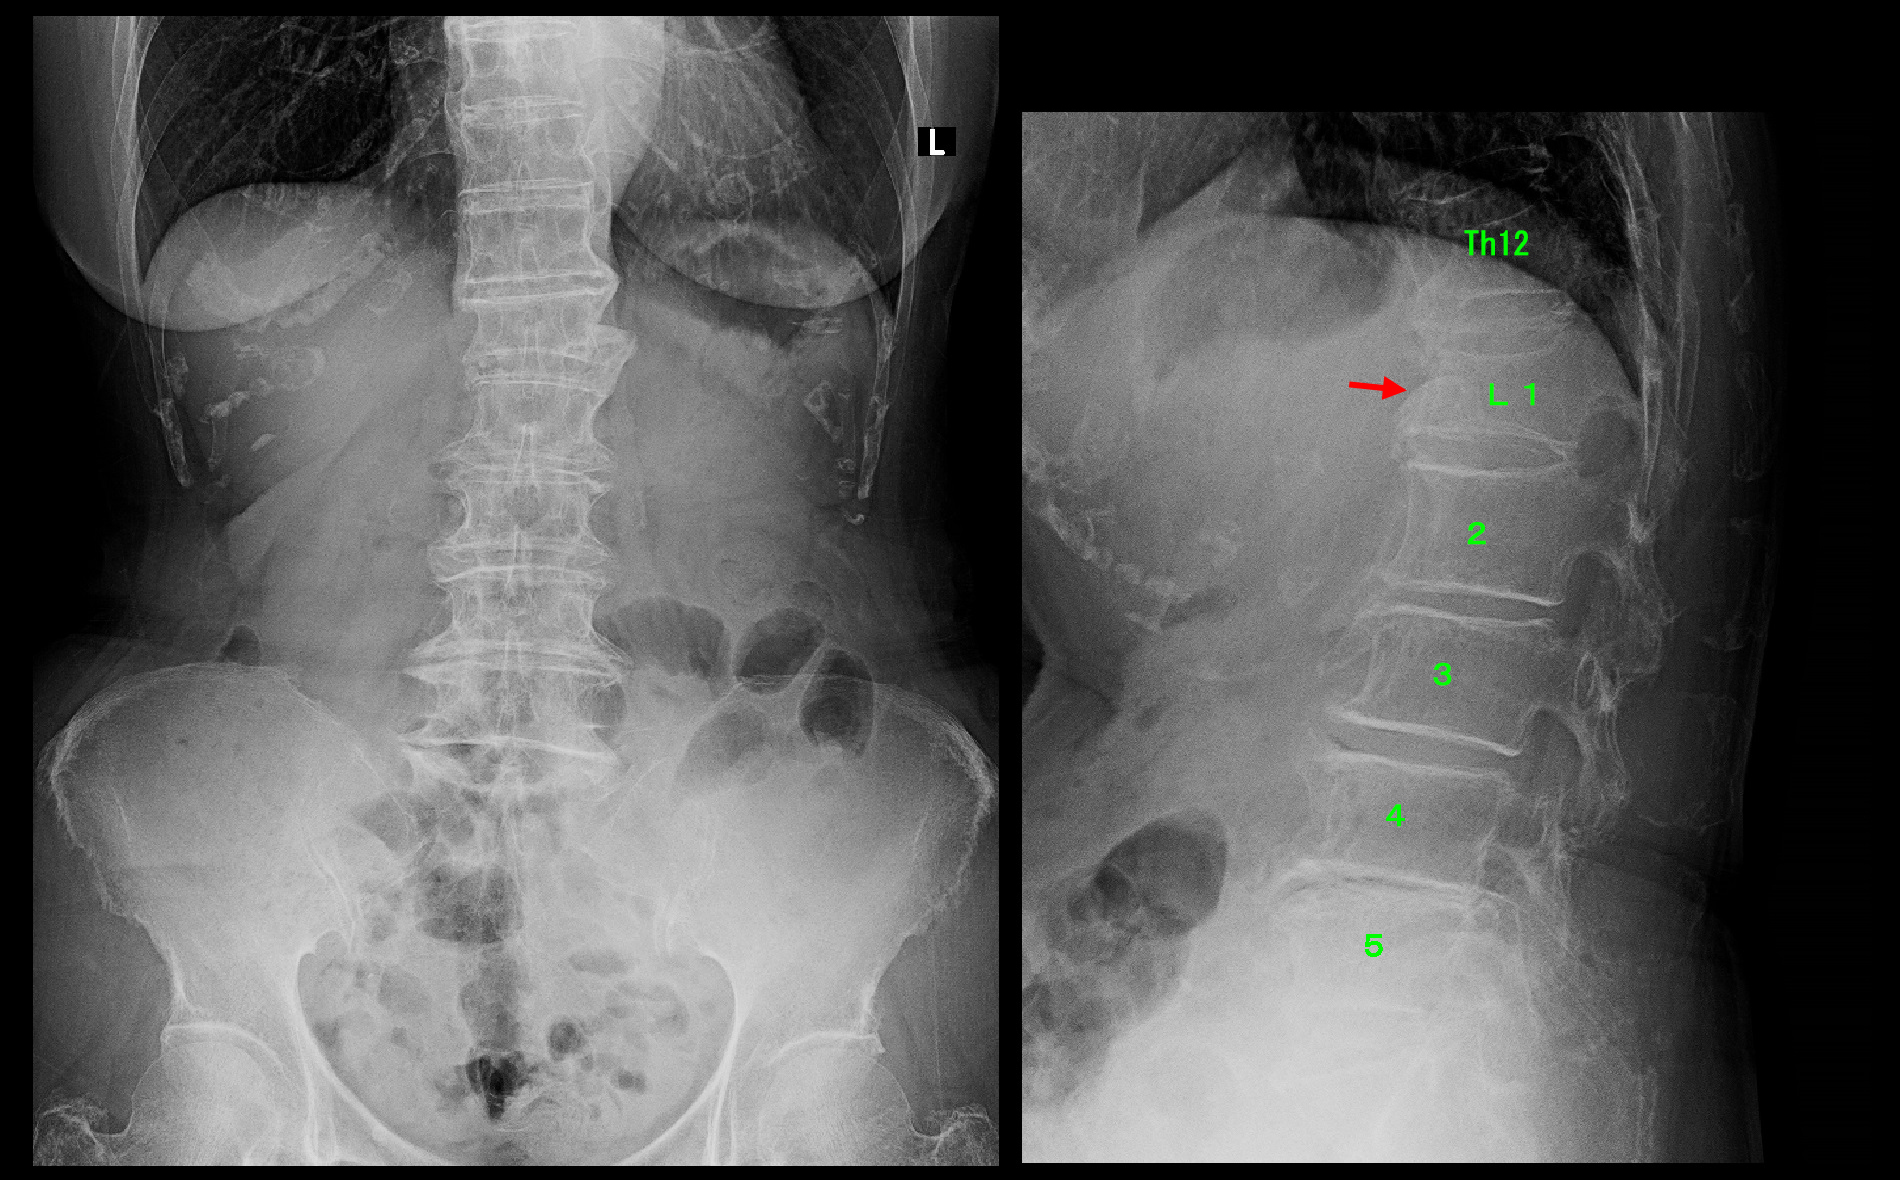

81才女Xp3.jpg

1月11日(初診から2か月後)には患者さんは腰痛は大分楽になったと述べていましたが、レントゲン像ではL1椎体の上の第12胸椎の扁平化が確認され(赤矢印)、MRI検査を行いました。

81才女MR2.jpg

MRI検査(T1条件)では、第12胸椎が低輝度化しており、圧迫骨折を発症したことが確認されました。